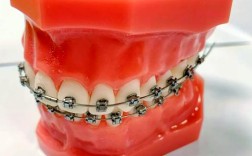

- 传统金属托槽矫正: 经济实用,适用范围广。

- 自锁托槽矫正: 复诊间隔可能延长,舒适度相对较好,效率可能更高。